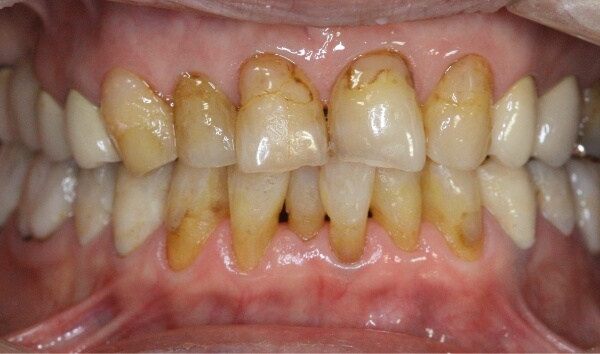

上下の前歯に、大きな隙間があります。

術前